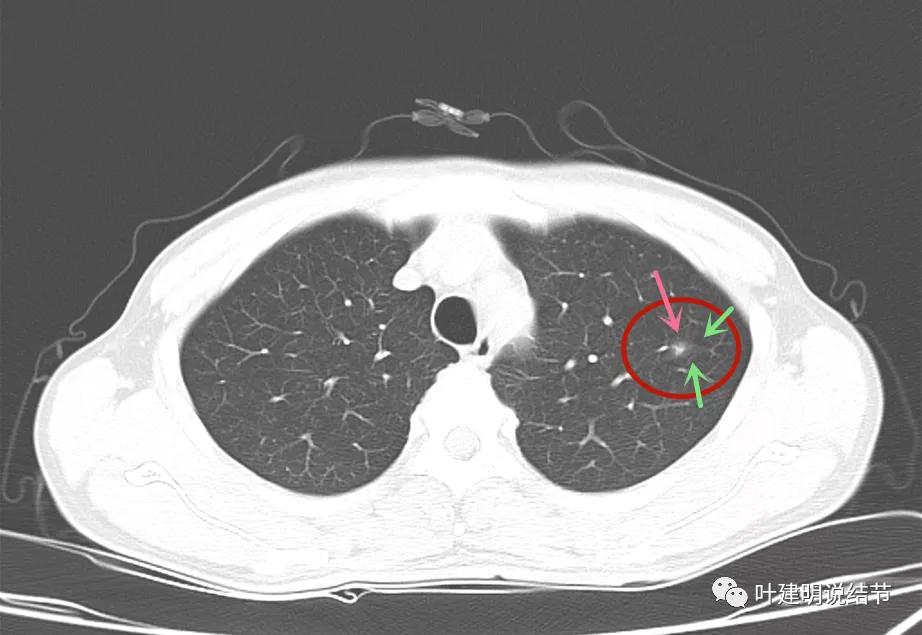

先来看2021年8月的:

病灶1:左上叶结节是混合磨玻璃,但磨玻璃部分密度很低,实性部分密度高,感觉偏散,没有明显收缩力,瘤肺边界模糊不清

病灶2:左下叶极淡的磨玻璃结节,中间似有空泡或偏低密度,但血管似乎有点走向病灶的样子

病灶3:右上叶前段微小淡磨玻璃结节,甚小,2-3毫米许,影像特征不明显,轮廓较清。